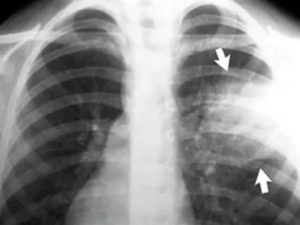

Снимок демонстрирует очаги воспалительного процесса на маленьких участках двух легких.

Очаговая пневмония характеризуется тенями неоднородной структуры, которые хорошо видны на снимке. Одинокие или множественные участки обычно размером до 1,5 сантиметра, неоднородные без четких границ.

Признаками очаговой пневмонии являются:

- нечеткие контуры тени;

- наличие жидкости в пораженной зоне;

- неоднородность участка инфильтрации.

Очаговая пневмония на рентгене характеризуется наличием жидкости в реберном синусе на стороне поражения. Среди всех форм пневмоний, очаговая является самой распространенной и зачастую она следует как осложнение после перенесенных респираторных заболеваний.